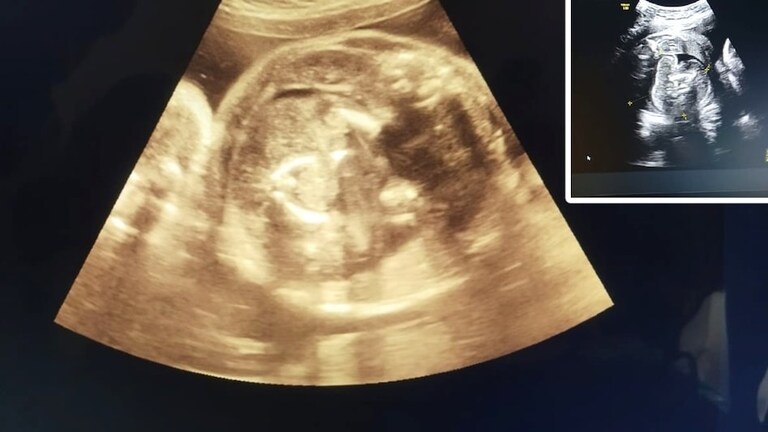

ज़का खान, बुलढाणा: बुलढाणा सरकारी रुग्णालयात गर्भवती महिलेची सोनोग्राफी ही प्रचंड चर्चेत आली आहे. जेव्हा डॉक्टरांनी सोनोग्राफी बारकाईने तपासली तेव्हा त्यांनाही धक्का बसला, कारण गर्भवती महिलेच्या गर्भाशयात बाळ दिसत होते. तसेच, या बाळाच्या पोटात देखील आणखी एक बाळ दिसत आहे.

खरं तर, दोन दिवसांपूर्वी, जिल्ह्यातील मोताळा येथील एका गावातील 9 महिन्यांची गर्भवती असलेली महिला (वय 32 वर्षे) ही सरकारी रुग्णालयात पोहोचली. तिथे डॉक्टर प्रसाद अग्रवाल यांनी गर्भवती महिलेची सोनोग्राफी केली. सोनोग्राफी करताना त्यांना त्या महिलेच्या पोटात एक बाळ दिसले आणि त्यासोबतच त्यांना त्याच बाळाच्या पोटात आणखी एक बाळ दिसले.

यामुळे जेव्हा डॉ. अग्रवाल यांनी त्या महिलेची आणखी तीन वेळा सोनोग्राफी केली तेव्हा त्यांना आढळले की तिच्या पोटातील बाळाच्या पोटात आणखी एक बाळ आहे.